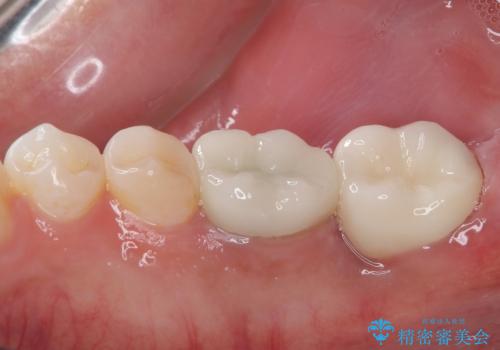

審美面、機能面共に満足していただけました。

舌側の虫歯が大きかったため歯茎の腫れが心配でしたが腫れもなく経過良好です。

引き続き矯正後の後戻りのチェックを行っていく予定です。